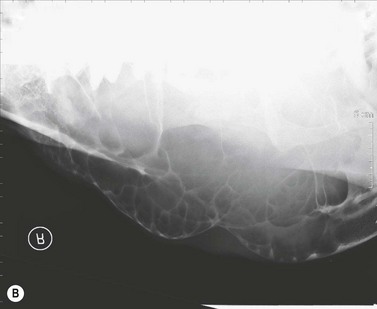

Clinical features

The condition is usually presented as a painful, hot, progressive swelling of the mandible with a characteristic ‘sun-burst’ radiographic appearance of bone lysis and irregular deposition of trabecular reactive new bone44 (Fig. 11.12). Pathological fractures can occur in affected bones.

Their radiographic appearance is highly suggestive, but biopsy provides the only definitive diagnosis. There is a characteristic combination of cortical bone destruction and periosteal new bone formation giving the area a ‘sunburst’ radiographic appearance.